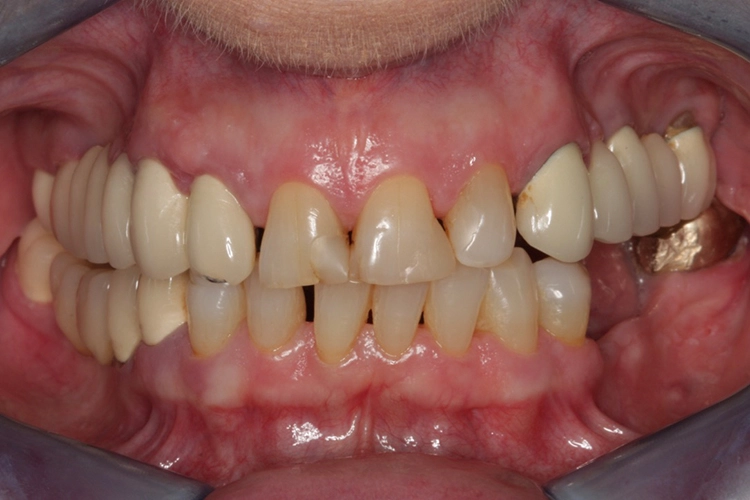

Die Kronen wurden auf den Implantaten verschraubt, um einer durch Befestigungszement induzierten Periimplantitis sicher entgegenzuwirken. Das klinische Abschlussfoto zeigt reizfreies Weichgewebe im periimplantären Bereich sowie eine ausreichende keratinisierte Mukosamanschette periimplantär (Abb. 20).

Die Verschraubung stellt eine wichtige Prävention gegen das Auftreten einer Periimplantitis dar. Das röntgenologische Abschlussfoto zeigt die knöcherne Regeneration des Defektes und gute Osseointegration der Implantate (Abb. 21).